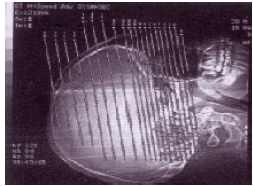

No planejamento tomográfico abaixo, pode-se afirmar que os cortes serão obtidos no plano